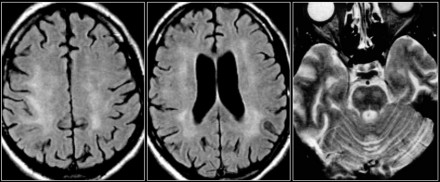

正常衰老性的退化

圖片五:正常衰老的腦部MRI成像:大腦溝回間隙增寬、腦室周圍出現(xiàn)帽狀和帶狀結(jié)構(gòu)(箭頭所示),在深部白質(zhì)中出現(xiàn)一些點狀病灶。

在正常衰老的腦部MRI成像中,我們可以看到:

? 腦室周圍出現(xiàn)帽狀和帶狀結(jié)構(gòu);

? 腦輕度萎縮,溝回和腦室增寬;

? 深部白質(zhì)中出現(xiàn)點狀病灶,有時甚至出現(xiàn)融合病灶(Fazekas量表分級為I~II級)。

腦室周圍帽狀結(jié)構(gòu)是側(cè)腦室前、后角周圍的高密度區(qū)域,與髓鞘褪色和血管周圍間隙增寬有關(guān)。腦室周圍的帶狀影是沿著側(cè)腦室室周出現(xiàn)的細小線狀病灶,與室管膜下角質(zhì)增生有關(guān)。

圖片六:白質(zhì)病變,F(xiàn)azekas分級為I、II 、III級

衰老過程出現(xiàn)白質(zhì)變化的臨床意義尚未完全闡明。多個腦血管危險因素與白質(zhì)病變有關(guān),除高血壓之外,其中最強的危險因素就是衰老。是否是生理性的白質(zhì)變化,取決于患者的年齡。

根據(jù)Fazekas評分量表,可將白質(zhì)變化分為不同的程度:

1. 輕度:點狀白質(zhì)損傷病灶,F(xiàn)azekas分級為I級。

2. 中度:融合的白質(zhì)損傷病灶,F(xiàn)azekas分級為II 級,在深部白質(zhì)中出現(xiàn)這種病灶可以認為是衰老過程中的正常生理性改變。

3. 重度:廣泛融合的白質(zhì)損傷病灶,F(xiàn)azekas分級III級,這種改變是病理性的。